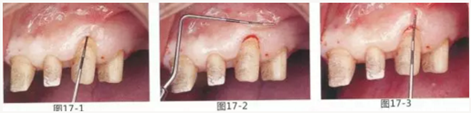

圖17-1~3 左上3的牙周袋探測值為3mm,角化牙齦寬度為2mm。也就是完全不存在附著齦,如果這種狀態(tài)下佩戴修復體的話,很有可能發(fā)生頸部暴露等問題。

圖17-4 左上1,2進行齦瓣根尖側轉移,左上3,4進行游離牙齦移植,在去除牙周袋的同時獲取附著齦。

圖17-5 牙周治療完成后的正面照。左上3,4部位處游離齦移植片的上端通過骨膜縫合固定在頰側嵴頂部。這樣可以使其愈合效果與齦瓣根尖側轉移相同。